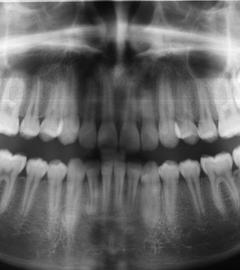

Ein weiterer Kritikpunkt ist, dass eine reine Zusendung von Alignern standardunterschreitend sei. Sie fordern: ein verpflichtendes Röntgenbild vorab gehöre zu einer solchen Behandlung ebenso dazu wie regelmäßige zahnärztliche Untersuchungen vor, während und nach der Behandlung. Dieser Standard sei aber nicht bei allen Anbietern gegeben. Risiken und Nebenwirkungen, wie Zahnwurzelentzündungen, Entzündungen im Zahnfleisch oder Parodontose könnten unter Umständen übersehen werden und zu einer Ausbreitung der Entzündung bis hin zu Zahnverlust führen. In einer kieferorthopädischen Praxis würde der Patient hingegen ausführlich befragt und ein Röntgenbild erstellt, um solche Folgen zu vermeiden.